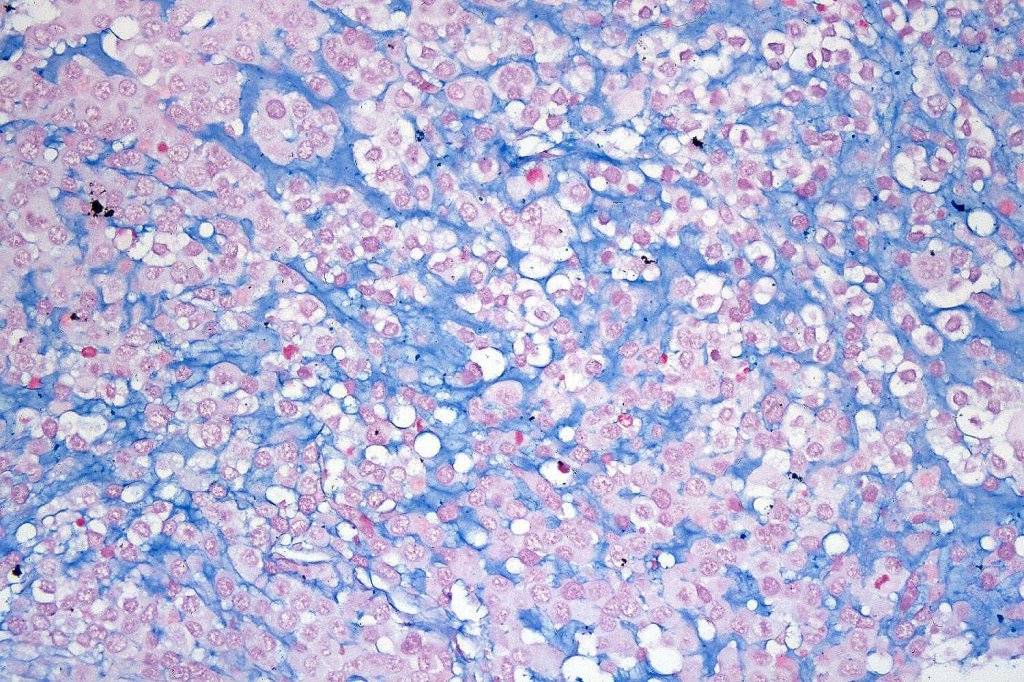

A rare variant of melanoma in which stromal cells produce excess acid mucopolysaccharides inprting a striking myxoid quality. The mucin is Alcian blue & colloidal iron positive, DPAS negative and the melanoma cells stain with typical markeres including S100 & HMB45. It may be seen in primary, recurrent or most often in metastatic lesions. The tumor cells are typically small although occcasionally they are epithelioid. Melanin is often sparse or even avsent making diagnosis difficult. In some examples, a pseudoglandular appearance is seen.

The differential diagnosis is very wide and can include numerous myxoid soft tissue tumors and epthelial mucin-secreting carcinomas. Diagnosis depends on clinical history, mucin stains and the judicious use of immunohistochemistry.